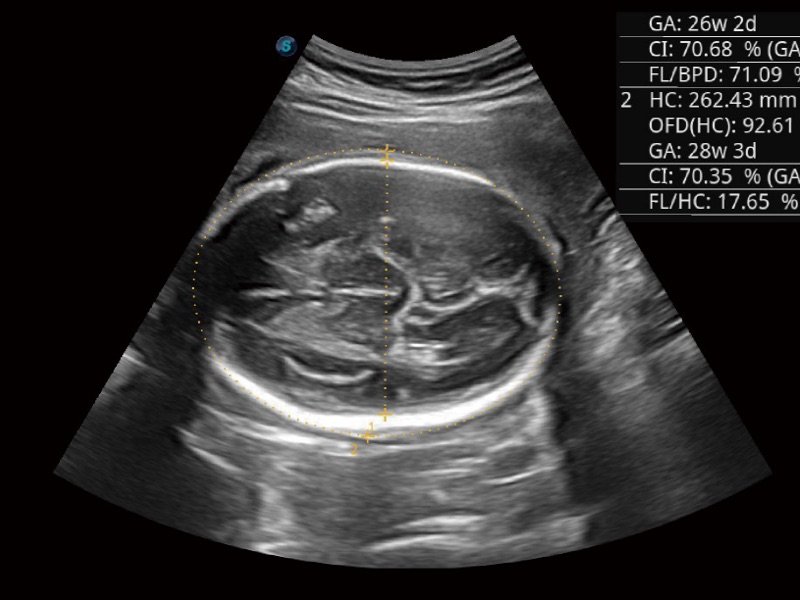

S-Live Silhouette

Durch den Einsatz einer virtuellen Lichtquelle und des Schattierungseffekts sieht S-Live Silhouette durch die Oberfläche hindurch und bildet die Umrisse von Knochen, Organen, Hohlräumen, Gefäßwänden und anderen inneren Strukturen scharf ab. Diese Funktion eignet sich hervorragend zur Erkennung der normalen Anatomie und zur Diagnose komplexer angeborener Fehlbildungen.